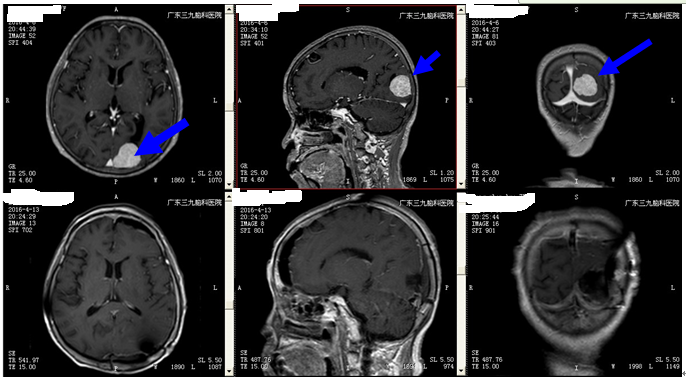

王阿姨,75岁,儿孙满堂,子女工作稳定,本应该含饴弄孙享天伦之乐,但是突如其来的头晕,扰了她的心情,在家休息未见缓解,遂去当地医院就诊,查头颅MR平扫+增强:1、左枕占位性病变,2、右侧基底节区、双侧放射冠区、双侧额叶脑梗死、缺血灶。予对症处理后,症状无明显好转。为求进一步治疗来,我院就诊。诊断:1、左枕占位性病变:脑膜瘤可能,2、高血压病3级(高危)

手术由神经外二科主任林涛主刀完成,在全麻下行左侧枕部脑膜瘤切除术,术后予营养神经、改善循环、保护胃肠道,康复理疗等系统治疗后,王阿姨头晕症状缓解,好转出院,病理回报提示:脑膜瘤。